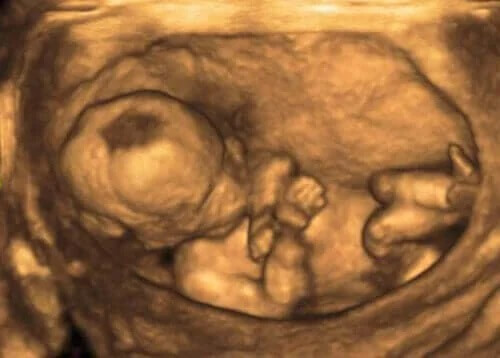

Fostervatten är den vätska som omger fostret inuti livmodern under graviditeten. Det har en mycket viktig roll i fostrets tillväxt och utveckling. I den här artikeln kan du läsa några mycket intressanta fakta om fostervatten som du kanske inte visste om.

Denna vätska ändrar sin sammansättning under tiden graviditeten fortskrider. Dessutom ökar volymen under graviditeten gång. I allmänhet ökar den fram till vecka 32. Den börjar dock minska vid vecka 40.

Fostret intar kontinuerligt denna vätska och kissar samtidigt ut den genom urinen. Detta innebär en reglering av mängden ämnen som finns i fostervattnet, vilket ger den nödvändiga balansen.